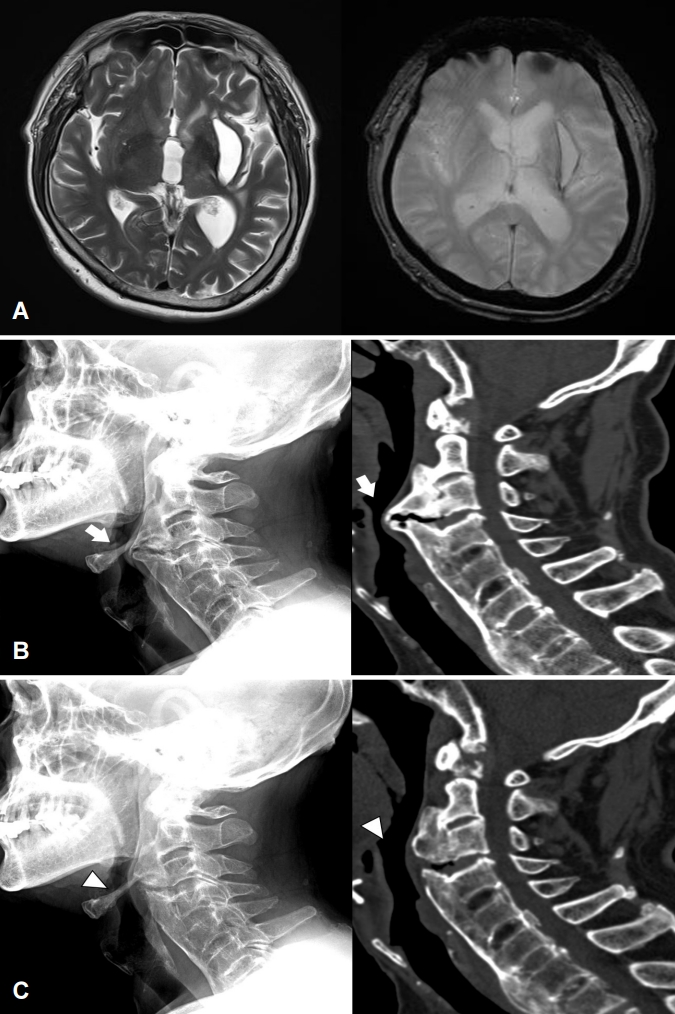

69세 환자가 수년 전부터 진행하는 삼킴곤란으로 내원하였다. 30년 전 좌측 기저핵의 뇌내출혈로 경한 구음장애와 우측 근력 Medical Research Council 척도 4등급이었다. 삼킴곤란은 액체류에서도 있었으나 고체류에서 더 심하였다. 혀의 움직임이나 다른 신경계증상의 악화는 없었고, 뇌 자기공명영상에서 새로운 병변은 없었다(Fig. A). 비디오투시연하검사에서 구강통과시간 연장 및 인두기에서 후두거상, 후두개 후방경사 저하가 있었으며 경추의 전방골극이 관찰되었다. 경추 X선검사, 경추 CT에서 경추 2-6번 부위의 전방골극과 전종인대골화증으로 인한 인두와 식도의 압박이 확인되었다(Fig. B). 경추 2-4번 부위의 골극을 수술로 제거 후 삼킴곤란은 일부 호전되었다(Fig. C).